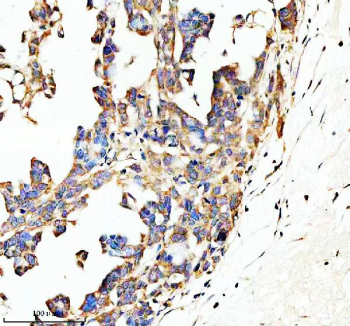

Immunohistochemical staining of SPON1 using anti-SPON1 antibody. SPON1 was detected in a paraffin-embedded section of human ovarian cancer tissue. Heat mediated antigen retrieval was performed in EDTA buffer (pH 8.0, epitope retrieval solution). The tissue section was blocked with 10% goat serum. The tissue section was then incubated with 2 ug/ml rabbit anti-SPON1 antibody overnight at 4oC. Peroxidase Conjugated Goat Anti-rabbit IgG was used as secondary antibody and incubated for 30 minutes at 37oC. The tissue section was developed using an HRP secondary and DAB substrate.